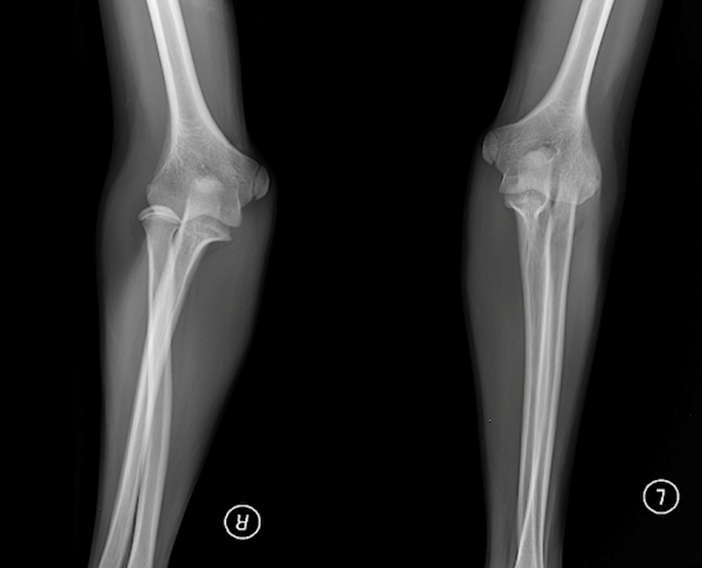

РОЗПІЗНАЙТЕ НА РЕНТГЕНОГРАМІ СУГЛОБ, ЩО СКЛАДАЄТЬСЯ З ТРЬОХ СУГЛОБІВ, ЯКІ МАЮТЬ СПІЛЬНУ КАПСУЛУ.

варіанти відповідей